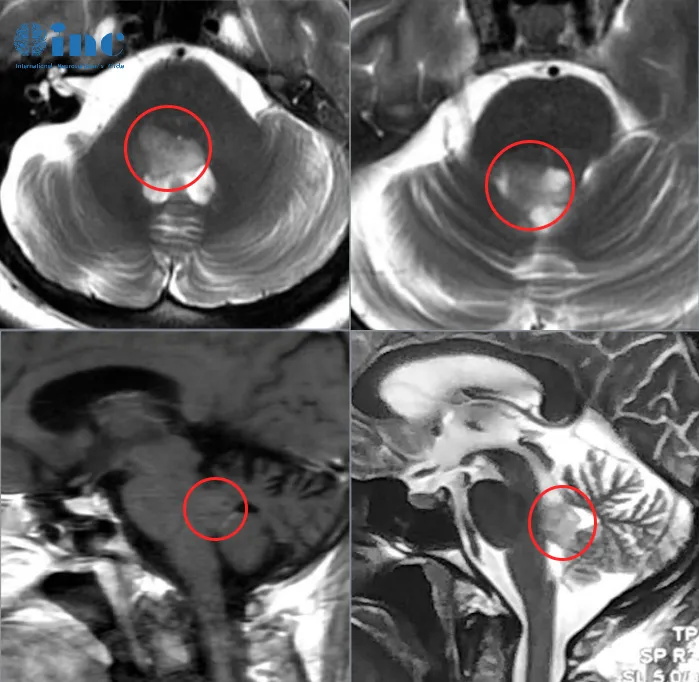

41岁的荣女士2022年11月出现腹泻、呕吐、头晕等症状,就诊于当地医院,行颅脑CT检查,提示无异常,遂对症保守治疗,慢慢好转。没想到过了一个月常规体检时,颅脑磁共振提示四脑室占位性病变。四处咨询了很多医生,从北京到香港,但问诊的结果总是让她无法满意。“手术风险大、保守治疗”这样的话,荣女士已经听了太多。难道医学如此发达的今天,无法找到一位对于治疗有信心的医生吗?为了得到更好的治疗,荣女士开始搜寻关于治疗疑难位置脑瘤的国际专家,此时INC巴教授进入了荣女士的视野。这场来自德国的视频咨询,也将为荣女士带来新的治疗选择和生机。

▼可以先观察一阵不做手术吗?手术风险大吗?

巴教授远程评估:肿瘤就会越来越大,并且肿瘤会越来越深入脑干内部。直到有一天,会达到无法来做手术治疗的地步,这就是我为什么建议你尽快做手术,而不是选择等待。

为了保护脑干在这个位置的神经功能(主要是六颅神经和七颅神经,即是眼球外展和面神经功能),手术切除应该是在合理的范围内。我很肯定,在保护神经功能的前提下,能得到90%以上的切除率。

▼巴教授远程邮件回复截选